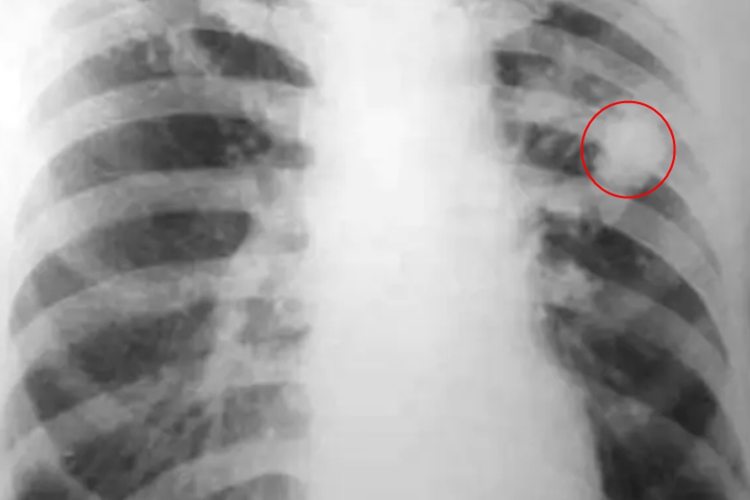

结核球:表现为球内有钙化灶或液化坏死形成空洞,同时多数有卫星灶,直径2-4cm,多小于3cm。